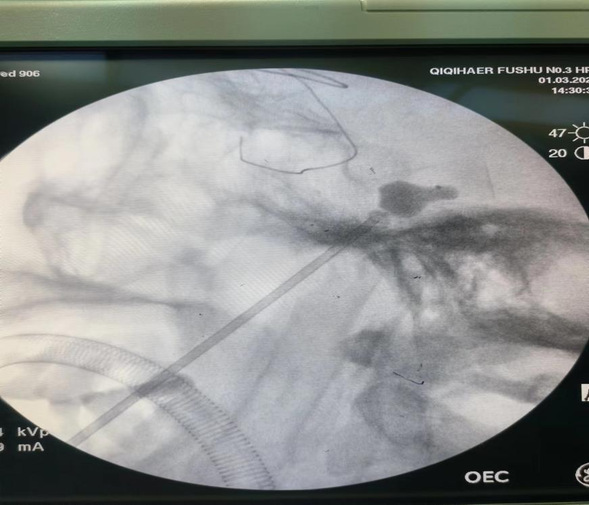

术中C型臂照相提示球囊呈梨形位于麦氏囊内,压迫2.5分钟,手术结束,总用时15分钟